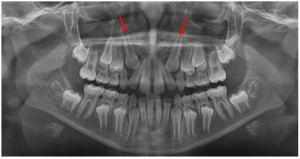

Compensação natural na Classe III

As discrepâncias esqueléticas verdadeiras, sobretudo as anteroposteriores, apresentam, na sua maioria, compensações dentárias em diversos graus. Normalmente nas Classes III de Angle observa-se uma protrusão dos incisivos superiores e a retroinclinação dos inferiores. Já nas Classes II, essa compensação apresenta-se numa relação inversa, onde os incisivos inferiores posicionam-se protruídos e os superiores retroinclinados.

Essas posições dentárias podem ser consideradas como uma tentativa natural de busca de equilíbrio entre os arcos dentários, o que pode mascarar pequenas discrepâncias esqueléticas, mas tornam-se ineficientes nas moderadas e severas. Nesses casos, um planejamento orto-cirúrgico restabelece não apenas o equilíbrio dentário, mas também o esquelético e, principalmente, o facial.